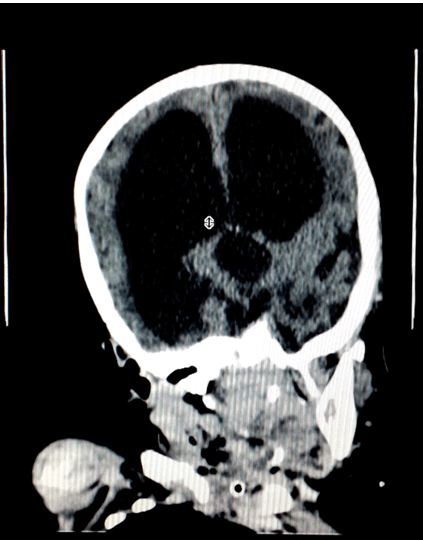

A five-year-old boy was presented to the emergency department with his parents with a history of falling from height. They lived in a rural area near Alexandria city. The father works as a farmer and the mother is a housewife, both of them were illiterate. The child was born term by normal labor. There was a history of an increased head size at birth, but the parents neglected this observation and they did not seek any medical advice although the head increased in size gradually over the time. Once the child was examined, a significant large head size of the child was noticed, which was not the complaint of the parents. The child was underweight (11 kg) and his height was less normal in his age group (80 cm). At the beginning the child was not alert but after a short while he gained his consciousness. There were signs of mental retardation, drowsiness, impaired speech, short attention span and impairment in physical coordination. The parents reported problems in his learning abilities. Upon examination of the head, its circumference was 66 cm. The scalp skin was shiny with apparent veins. Eye examination showed (setting sun sign). Computed tomography (CT) scan of brain revealed enlarged frontal and posterior horns of the lateral ventricles and enlarged third and fourth ventricles. Such bilateral huge ventriculomegaly is accompanied by severe brain parenchymal loss as illustrated (Figure 1) and (Figure 2). It was noticed also that the enlargement of the ventricles is out of proportion with sulcal atrophy, i.e., relative normal sulcal size, which is an indication of normal intracranial pressure. The images of the patient's brain were examined concerning the trauma that the child had after falling from height. The CT scan did not show any problem that happened due to the fall or any kind of hemorrhage. The parents were assured that the trauma did not cause any problem and were informed about such neglected case of hydrocephalus and that the child will most probably have a normal life span. They were told, however, that there is no cure for such condition and the patient was booked for an appointment at the rehabilitation center which will help the child to cope with the activities of the daily living and improve his cognitive function. The child was discharged without any surgical intervention after a full system examination which cleared the child. Moreover, we told the parents that they must attend a follow-up visit every six months with the neurology department in the hospital so that the child's symptoms are monitored. | ||||||